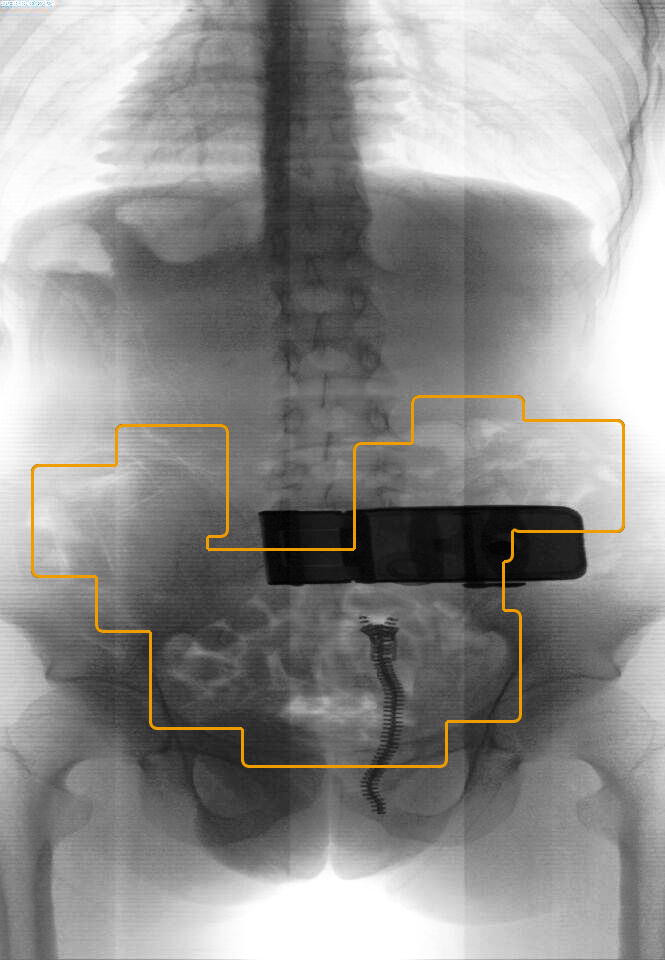

在传统固定式安检设备基础上大胆突破,并综合利用微剂量X光成像等多项技术,经多年开发研制而成,专门用于探测人体内外所携带违j品的一款可移动微剂量X光t视安检仪器。

产品能清晰、准确地查找定位出人体内外藏带的各类金属非金属d具、q支d药、危b物品、粉末颗粒、y丸j囊等金属、非金属物品物体,尤其对体内藏d具有良好的识别效果。

j准识别:可测物品种类多,检测全面,识别j准,尤其是体积较小、识别难度较大的缝衣针、d片、胶n、d品、黄金、玉石等物品。

隐私保护:成像图片不显示体表特征,保护个人隐私。

安全可靠:检测剂量低,单次检测剂量仅相当于医疗胸透的百分之一。